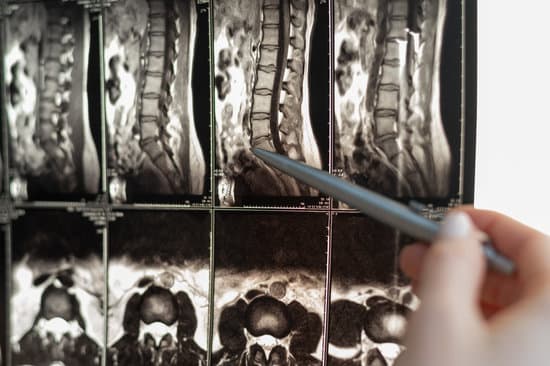

MRI: 연조직과 척수 상태를 정확하게 확인할 수 있어 손상의 정도와 위치를 진단하는 데 사용됩니다.